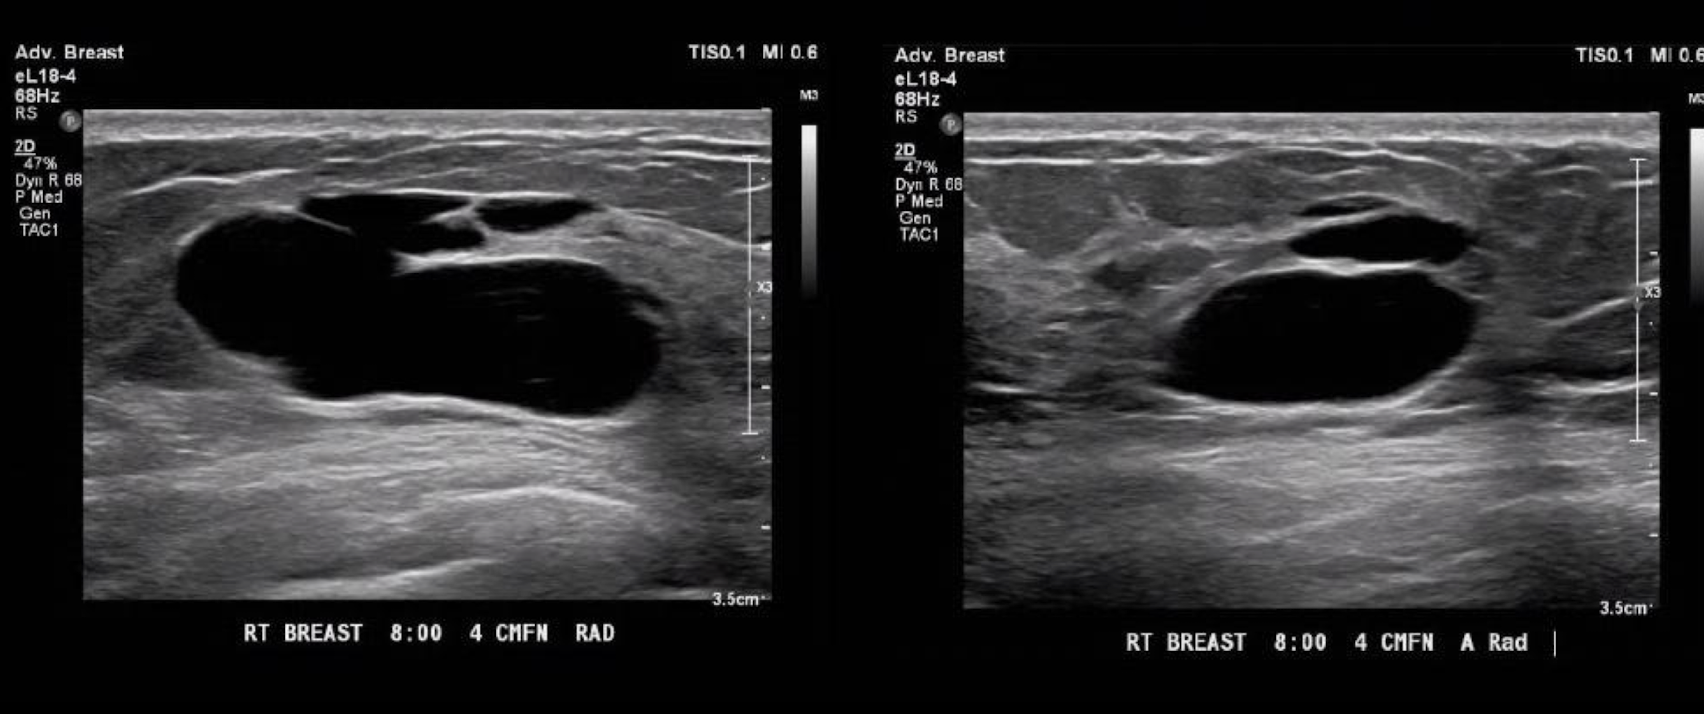

septated cyst$